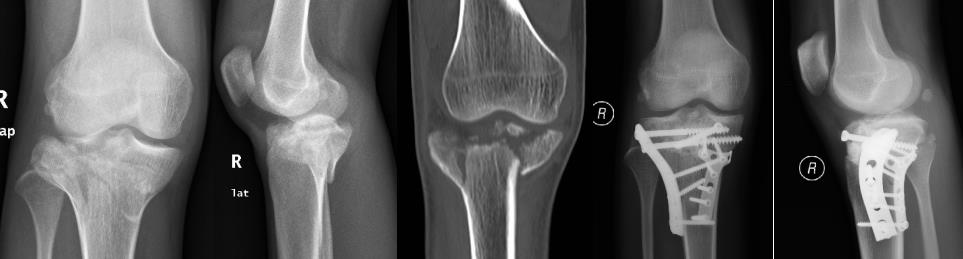

同一患者右胫骨平台骨折及左股骨长段骨折。微创复位内固定治疗,术后3周关节活动功能已恢复正常。